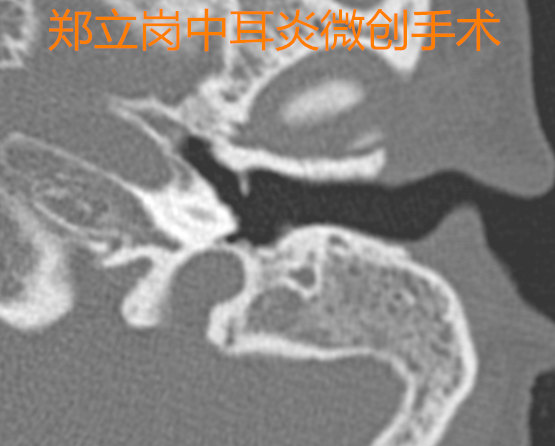

患者陈,女,34岁,广东佛山高明人。患者于2年前无明显诱因出现左耳流脓,间断性,脓液为淡黄色、无血丝、量不多、不臭,伴左耳听力下降,逐渐减退,无明显耳痛、耳鸣,无伴眩晕、恶心、呕吐等症状,予以药物治疗后症状可改善,但每遇感冒、耳道进水后易再次流脓。近1月来左耳未再流脓,今门诊以"左侧慢性化脓性中耳炎"收住入院,拟进一步手术治疗。患者左侧鼓膜大穿孔,残余鼓膜钙化明显,所以患者的听力较差。这次做的是全麻耳内镜中耳炎微创手术。插管全麻后就开始了手术,在耳内镜下不用做任何的体表切口,直接翻起外耳道鼓膜皮瓣,翻起皮瓣后可以看到锤骨柄的前方有明显的钙化组织固定锤骨柄。术中予以松解后听骨链活动恢复。取合适大小的耳屏软骨修剪后修补鼓膜,鼓膜修补好后检查了两遍确认没问题后就结束了手术。整个的手术用时约40分钟,非常的顺利。术后查房患者无明显的不适,无手术相关的并发症。